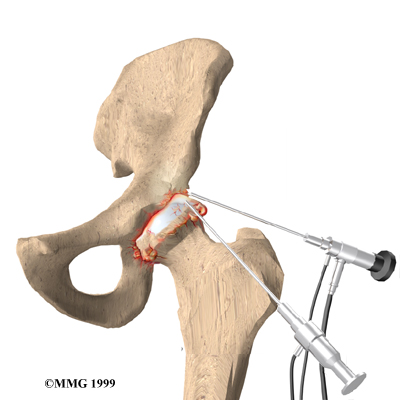

Arthroscopy

Surgeons can use an arthroscope to check the condition of the articular cartilage in a joint. An arthroscope is a miniature TV camera inserted into the joint though a small incision. While checking the condition of the cartilage, your surgeon may try a few different techniques to give you relief from pain. One method involves cleaning the joint by removing loose fragments of cartilage. Another method involves simply flushing the joint with a saline solution, after which some patients report relief.

This procedure is sometimes helpful for temporary relief of symptoms. Hip arthroscopy is relatively new, and it is unclear at this time which patients will benefit.